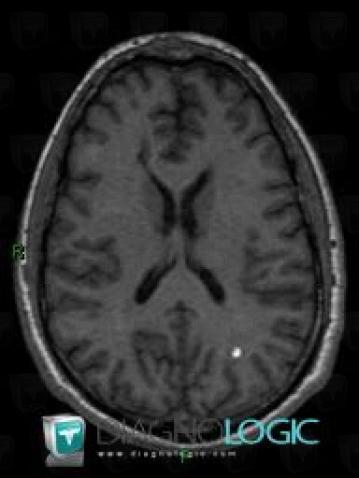

RiT radiology: Cavernoma

Cavernous hemangioma, also called cavernous angioma, cavernoma, or cerebral cavernoma (ccm) (when referring to presence in the brain) is a type of benign vascular tumor or hemangioma, where a collection of dilated blood vessels form a lesion. Report of two cases and review of the literature. Ajnr am j neuroradiol 1995;;

Cavernous hemangioma, also called cavernous angioma, cavernoma, or cerebral cavernoma (ccm) (when referring to presence in the brain) is a type of benign vascular tumor or hemangioma, where a collection of dilated blood vessels form a lesion. Cerebral cavernous malformations (ccms) or cavernous angiomas (omim #116860) are vascular malformations that occur in the cns, most often in the brain. Familial form of intracranial cavernous angioma: Sporadic cavernous angiomas are usually associated with a venous angioma, which is another type of vascular anomaly that can develop in the brain.